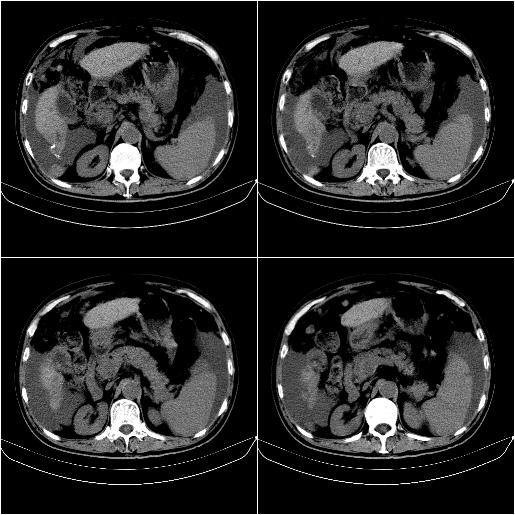

标题: CT21651:M,67Y,肝癌9月,介入术后3月。

m,67y,肝癌9月,介入术后3月。现腹胀、纳差、腹泻。

情况不好,门静脉癌栓、腹膜转移。

1)肝癌介入治疗术后碘油沉积不良。2)门静脉瘤栓形成,腹膜广泛性转移。3)肝硬化,脾大,腹水。4)慢性胆囊炎。